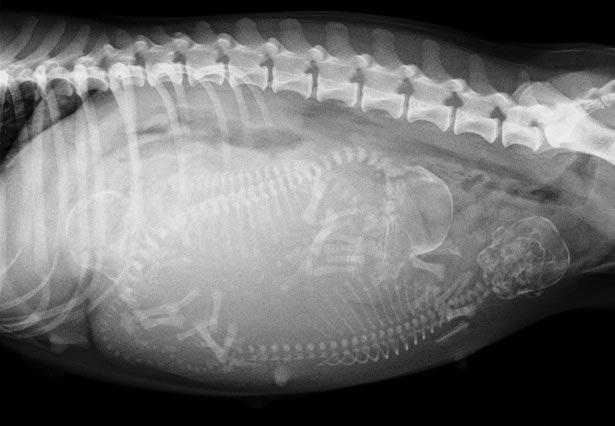

- На сорок восьмые сутки с помощью рентгеновского обследования можно определить количество щенков.

Плоды полностью сформировались, и на этой неделе можно заметить их активные движения. С помощью рентгеновского исследования возможно узнать количество эмбрионов.